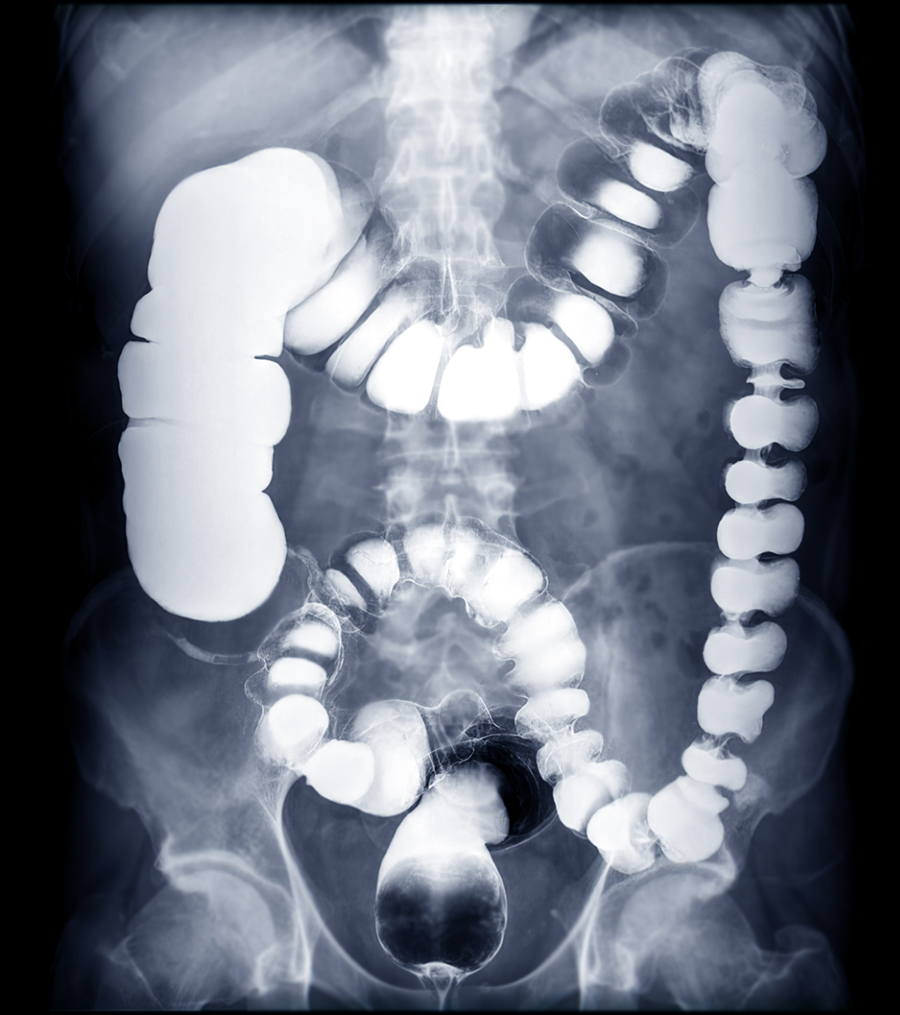

BE or barium enema image or x-ray image of large intestine showing anatomical of colon for detect Colon cancer .